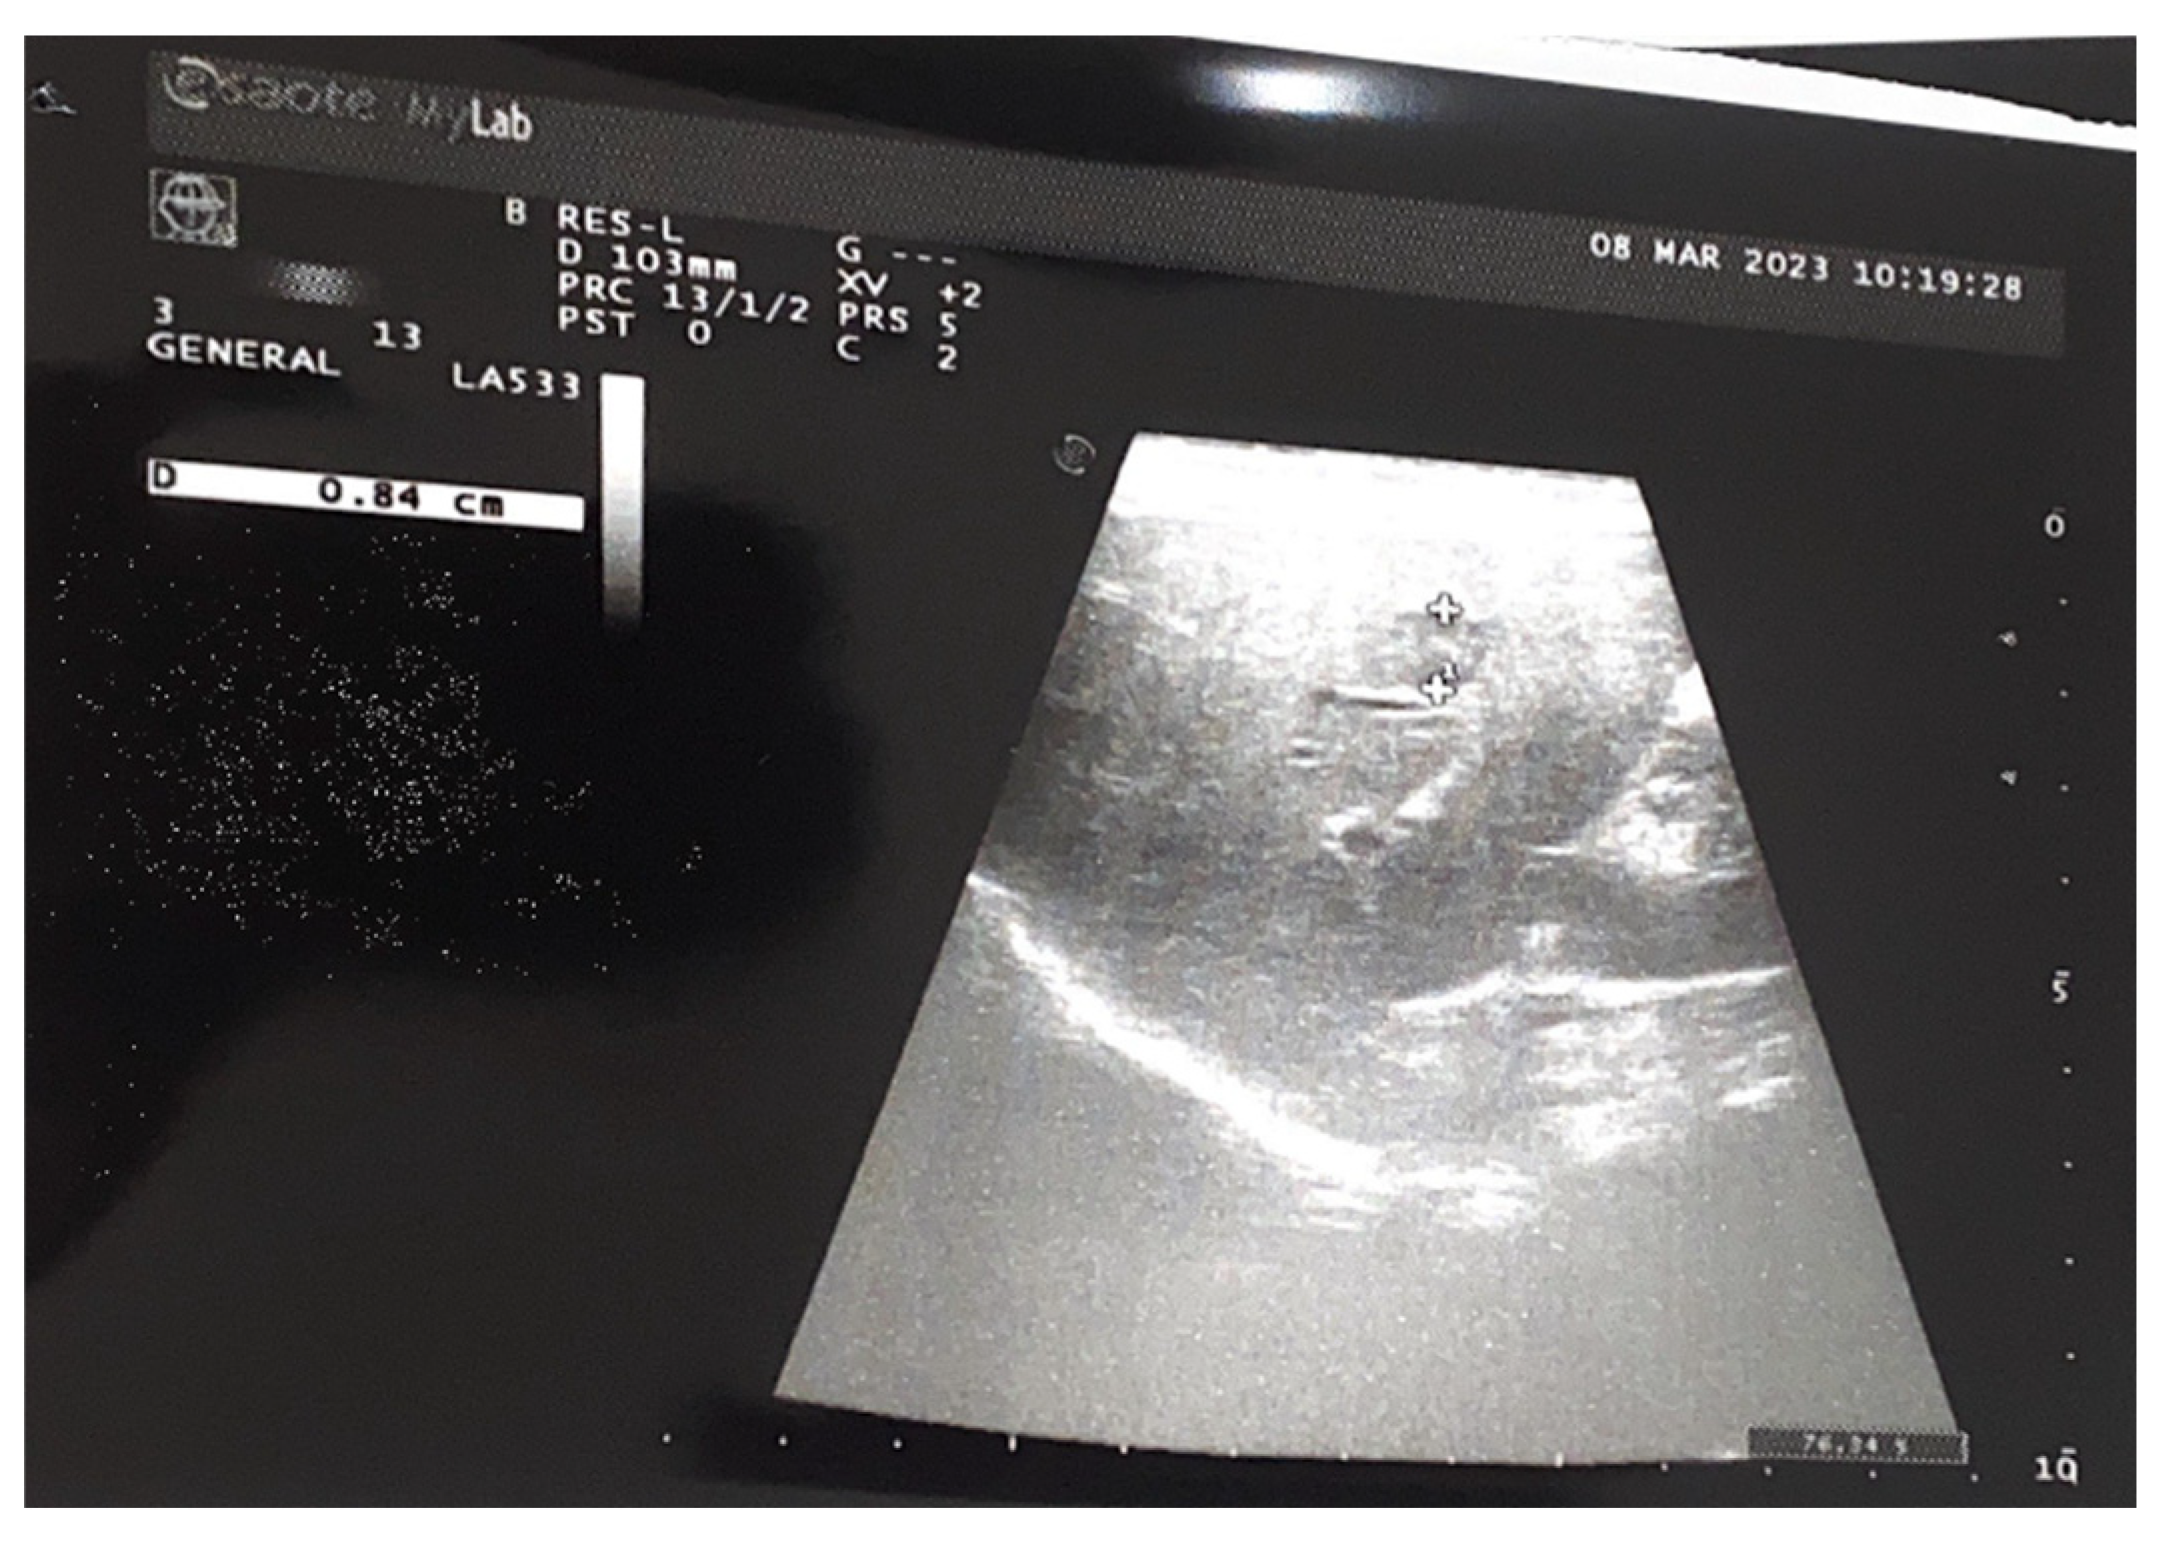

Figure 5. Sparse peripheral vascularization of the lesions.

Preprints 73814 g004

Preprints 73814 g002